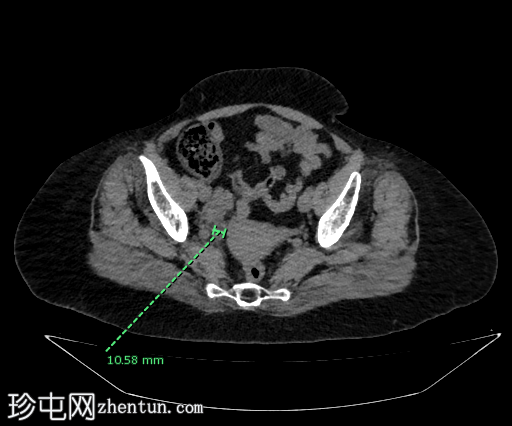

轴位

平扫

阑尾中段可见一放射性不透光阑尾粪石(冠状位和矢状位图像均可见),导致远端扩张。阑尾尖端直径达10 mm,呈充满液体的形态,周围可见脂肪条索,提示阑尾尖端炎。阑尾近端外观正常。